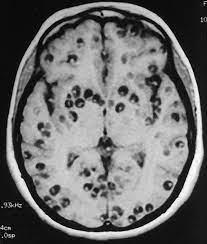

Particularidades da interação com o hospedeiro:

Humanos que ingerem ovos de T. solium figurarão como hospedeiros intermediários do agente, cujas larvas (cisticercos) tipicamente se alojam na musculatura estriada e SNC (neurocisticercose).